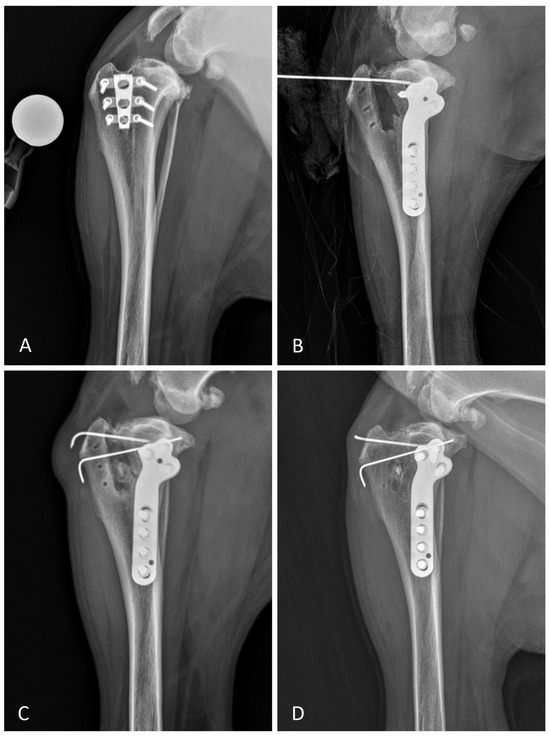

Tibial Plateau Leveling Osteotomy following Tibial Tuberosity Advancement Cage Removal: A Case Report

2. Materials and Methods

2.3. Surgery

2.4. Follow-Up

3. Results